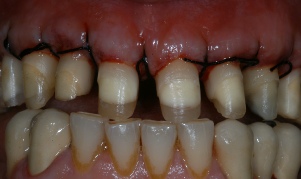

ΧΕΙΡΟΥΡΓΙΚΗ ΕΠΙΜΗΚΥΝΣΗ ΜΥΛΗΣ ΔΟΝΤΙΩΝ ΠΡΙΝ ΤΗΝ ΠΡΟΣΘΕΤΙΚΗ ΑΠΟΚΑΤΑΣΤΑΣΗ

ΠΡΙΝ

ΜΕΤΑ